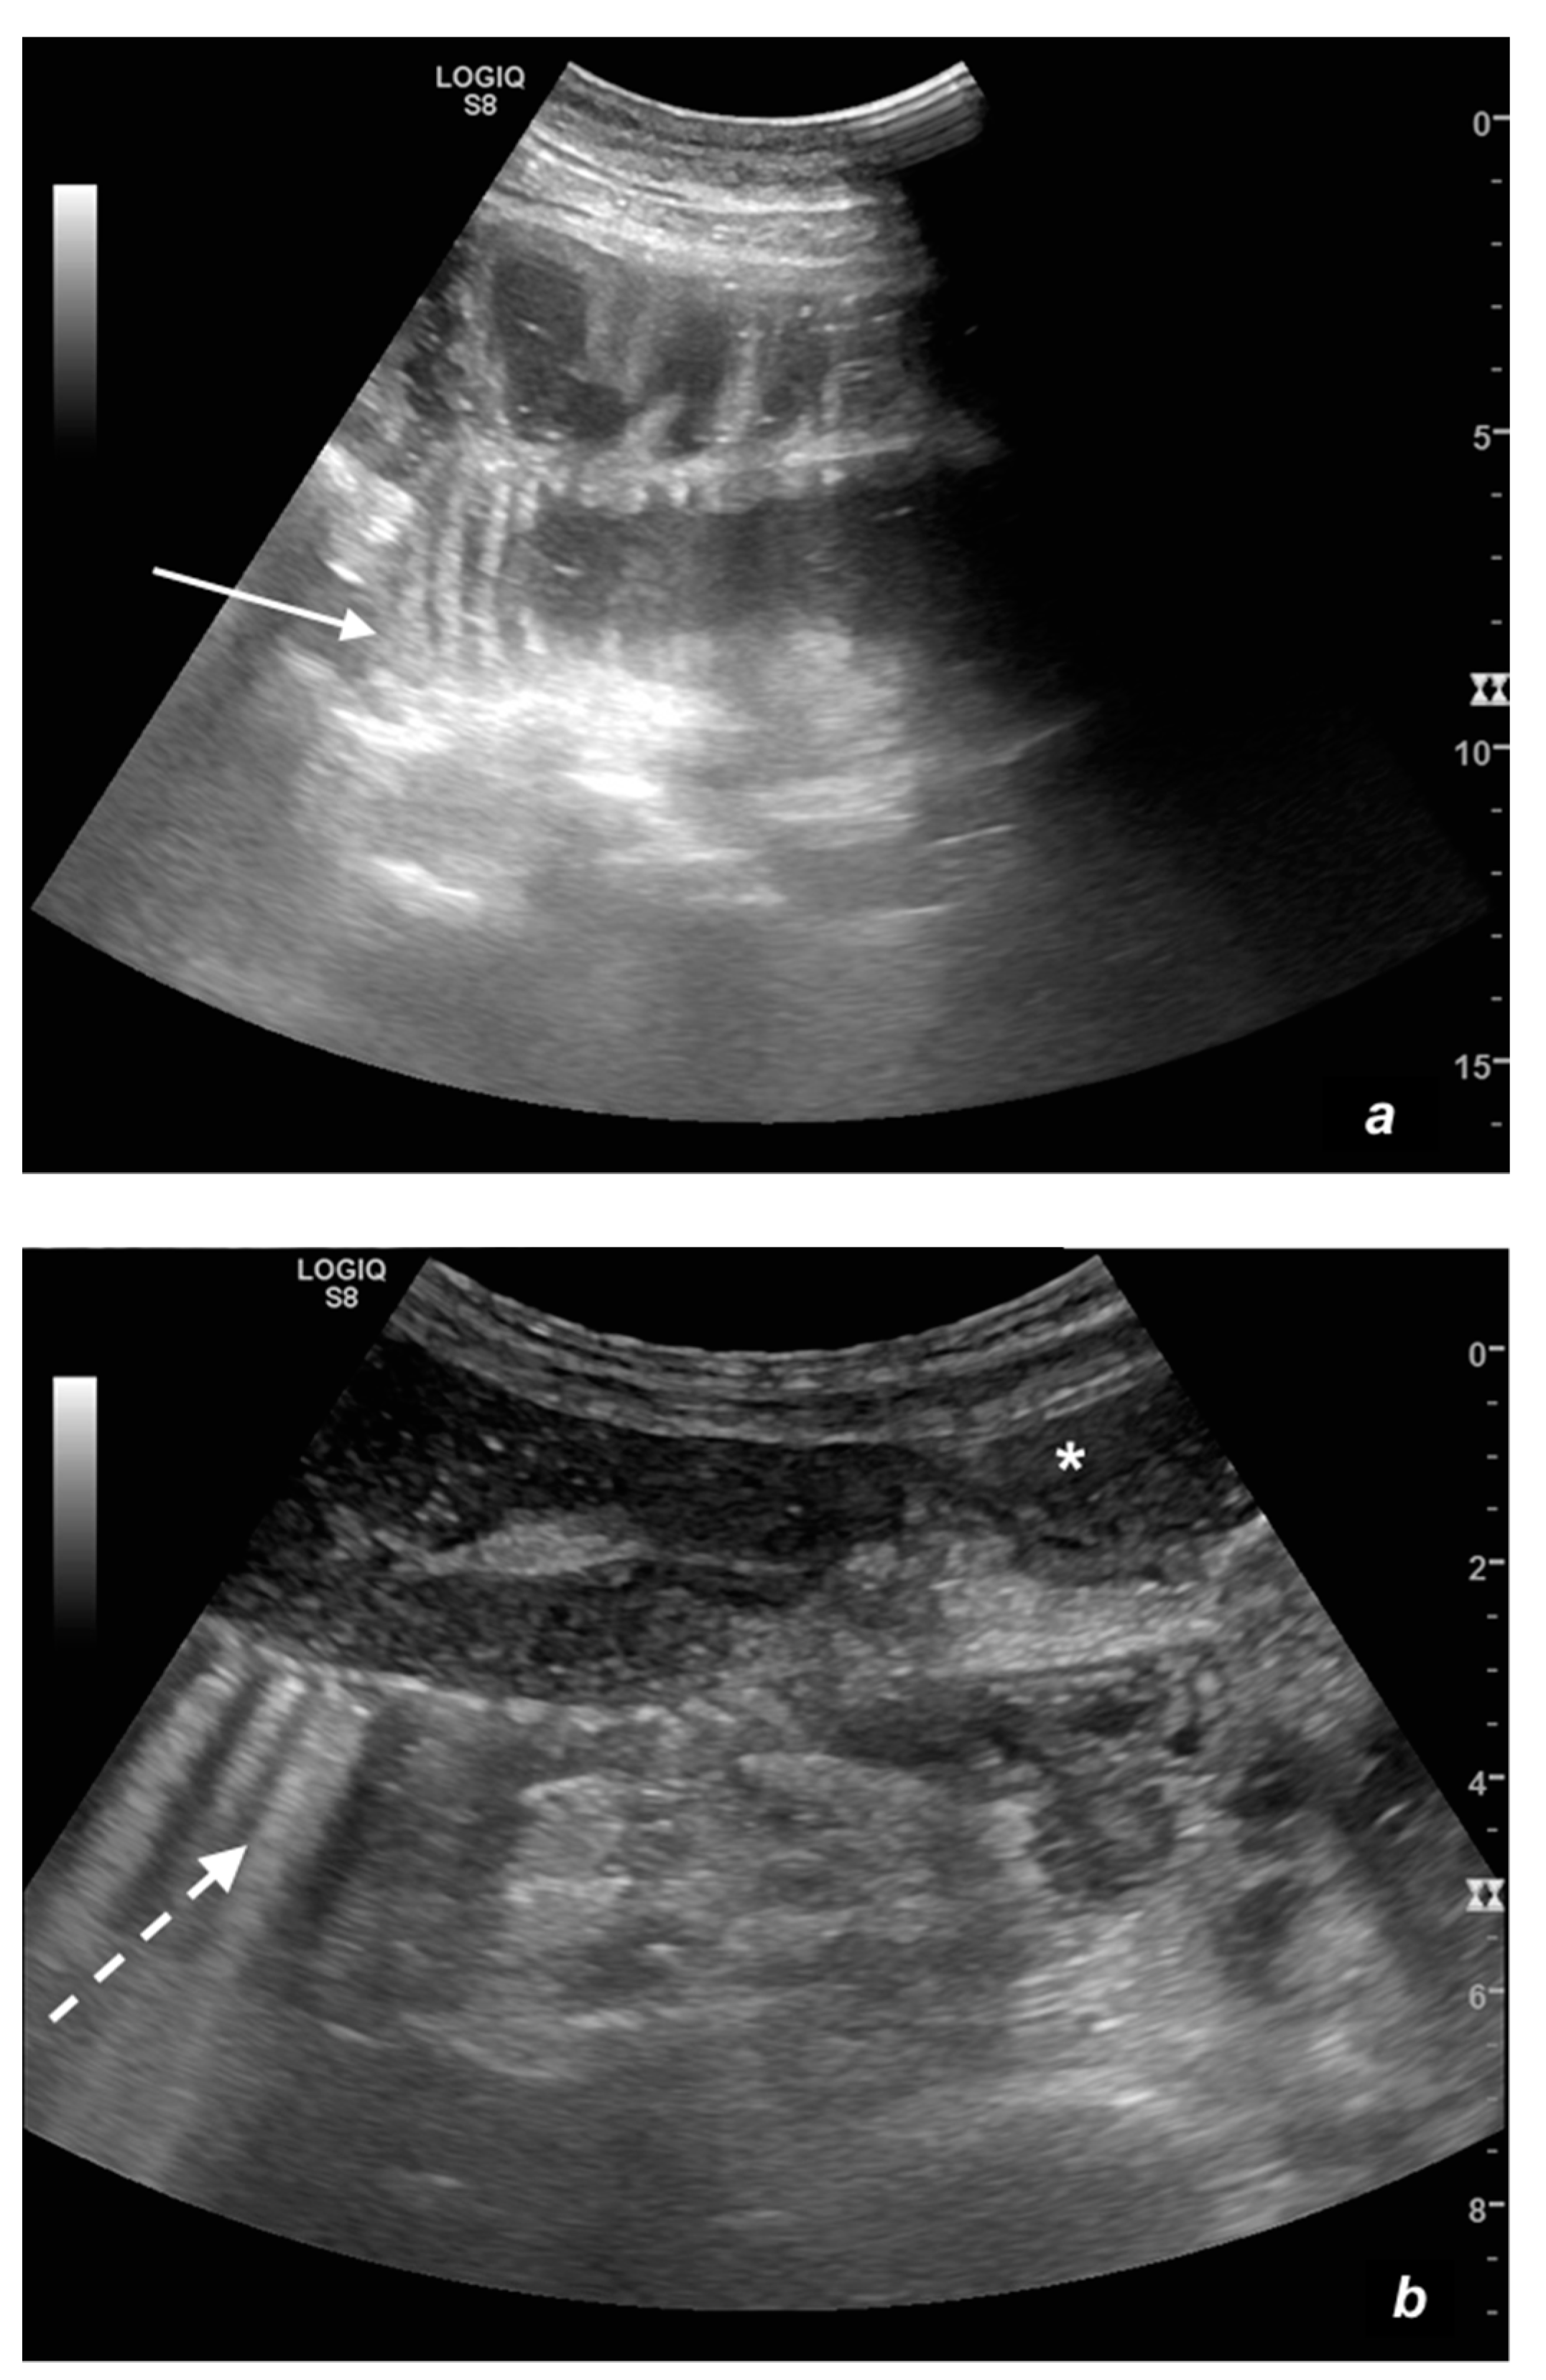

Figure 1.

(a,b). A simple SBO. Ultrasound images show fluid-filled, dilated small bowel loops (a,b) with hyper-kinesis and hyper-representation of valvulae conniventes (white arrow) (a); tail comet artifacts are visible due to air-fluid levels (dashed arrow) (b) and groups of bowel loops with severe differences in diameter (‘bowel jump diameter’) are evident more superficially (*) (b). No free fluid was detected in the abdominal cavity or between bowel loops.